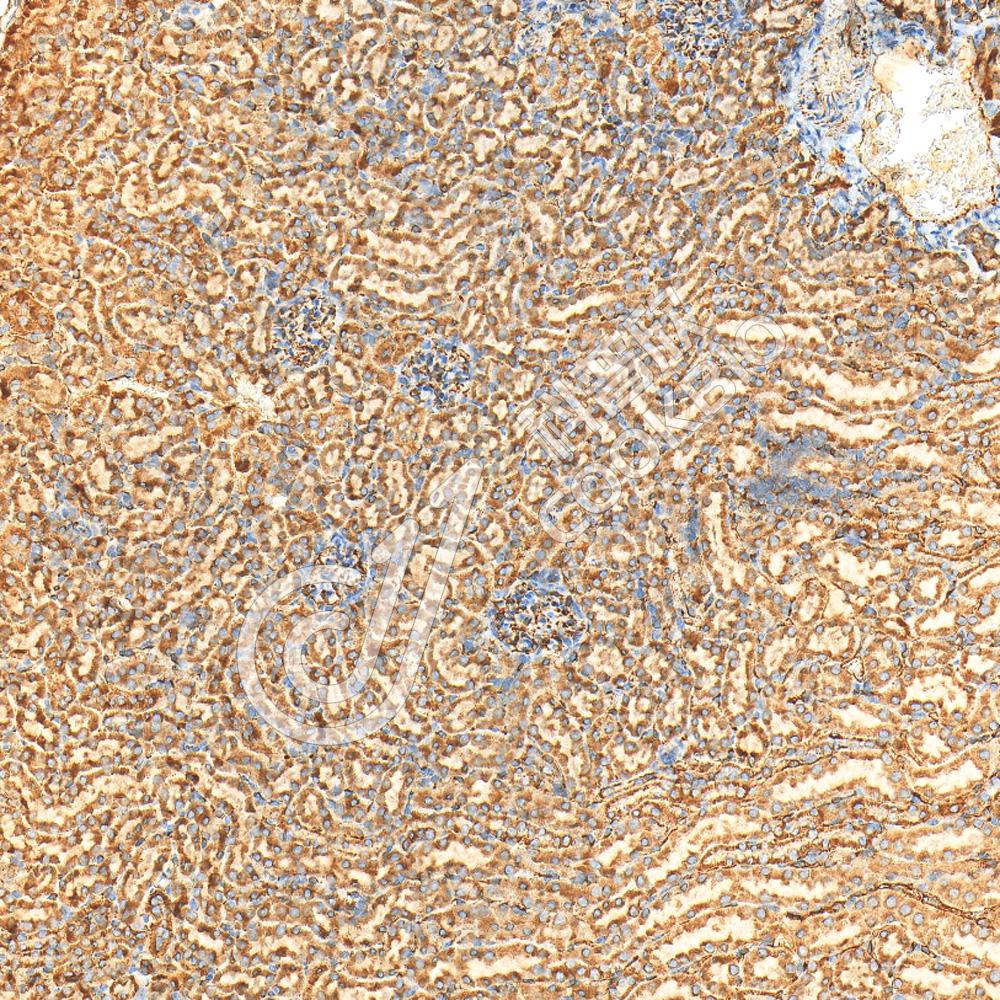

IHC检测LAS2蛋白(货号 K1345204).

样品: 小鼠肾, 4%多聚甲醛 (货号KSG1101) 固定12-24小时.

抗原修复: Tris-EDTA抗原修复液(pH 9.0) (KSG1203), 98℃, 20分钟.

—抗: 1: 1300稀释, 4℃ 孵育过夜.

二抗: S-vision免疫组化多聚二抗(山羊抗兔),即用型 (货号KB3906), 室温孵育20分钟.